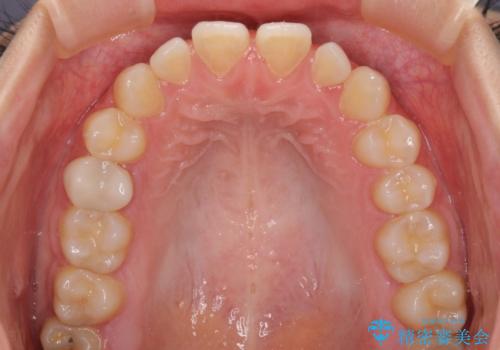

隙間だらけの歯列 インビザラインで改善

- 前歯の上下スペースと前歯の隙間を気にして来院された患者様です。

飲み込みや話をするときに舌を突出させる癖が強くあり、それが原因でスペースが空いていました。

舌癖を改善するためのトレーニングを行いながら、インビザラインにより上下の前歯の隙間を閉じていくこととしました。